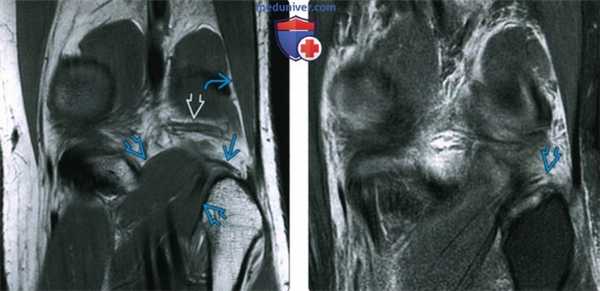

(Слева) На рисунке косого бокового среза показан полный разрыв объединенного сухожилия. Отмечается сжатие малоберцовой коллатеральной связки (МБКС), которая лежит кпереди от двуглавой мышцы бедра (ДМБ). Разрывы ДМБ возникают реже чем разрывы МБКС.

(Справа) МРТ латеральной поверхности колена, PDBИ, режим подавления сигнала от жира: определяется полный отрыв МБКС от головки малоберцовой кости с разрывом тяжелой степени или полным разрывом ДМБ. (Слева) МРТ Т2ВИ, режим подавления сигнала от жира, коронарный срез: у этого же пациента определяется гиперинтенсивный сигнал в области разорванного места прикрепления МБКС к головке малоберцовой кости. Проксимальная часть МБКС прикрепляется к латеральному мыщелку бедренной кости и является неповрежденной. Часть ДМБ объединенного сухожилия не попала в срез.

(Справа) MPT PDBИ, режим подавления сигнала от жира, аксиальный срез: у этого же пациента определяется разрыв МБКС непосредственно проксимальнее места ее прикрепления к головке малоберцовой кости. Волокна ДМБ частично разорваны. Латеральная капсула сустава не повреждена.